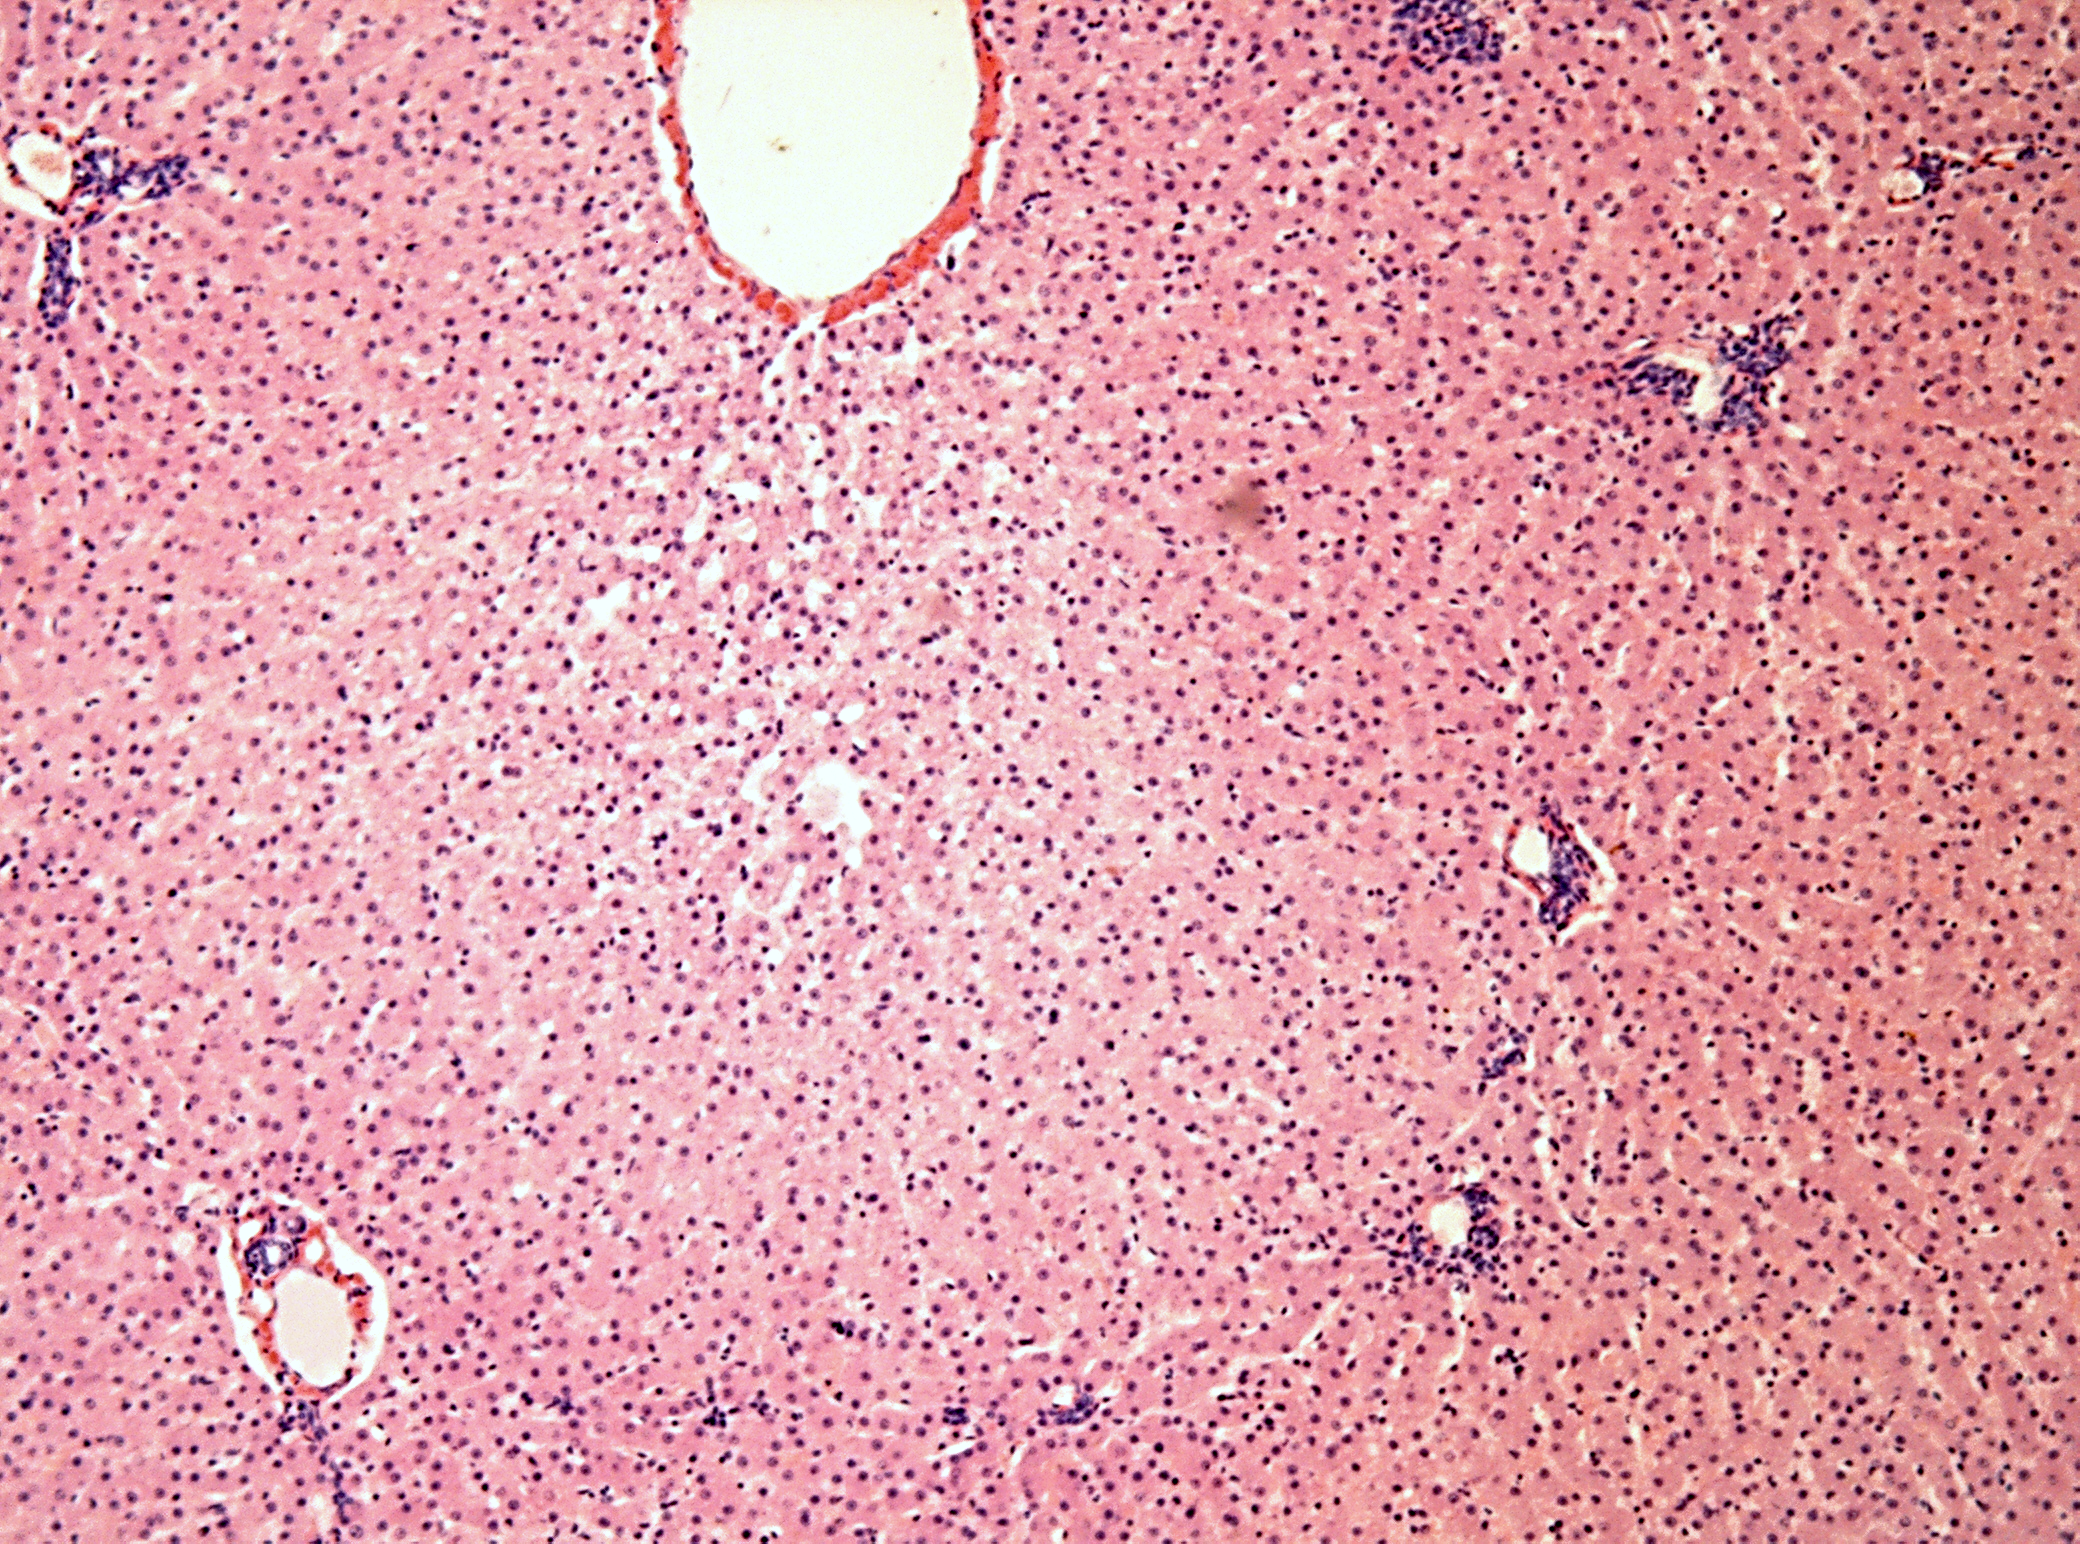

Микропрепараты: Лимфогранулематоз и Нодулярный Склероз

Раздел: Секреты мастерства